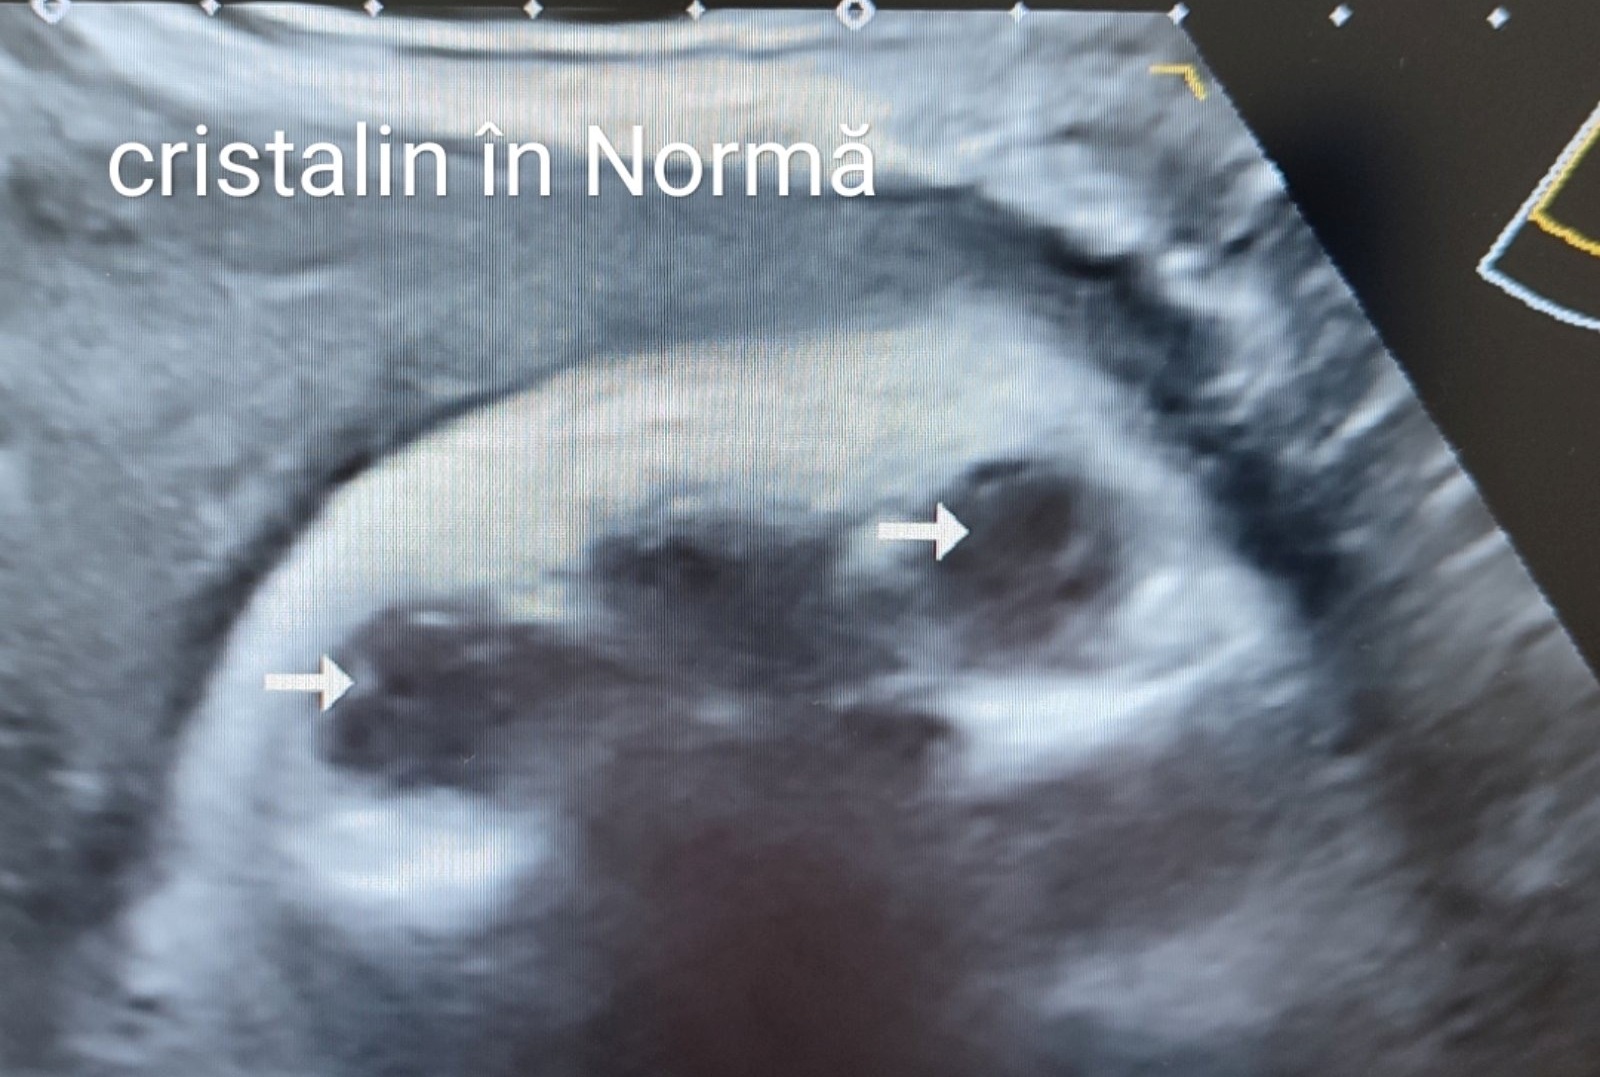

În cazul nostru, ecografia efectuată pe parcursul lunii iunie curent de către medicul imagist Svetlana Basova, la termenul 38 de săptămâni de sarcină a evidențiat la Cristalinul ochiului drept - o creșterea punctiformă a ecogenității în regiunea centrală a cristalinului (cataractă nucleară) iar la Cristalinul ochiului stâng – s-a determinat îngroșarea și creșterea ecogenității inelului periferic, completă (cataractă corticală).